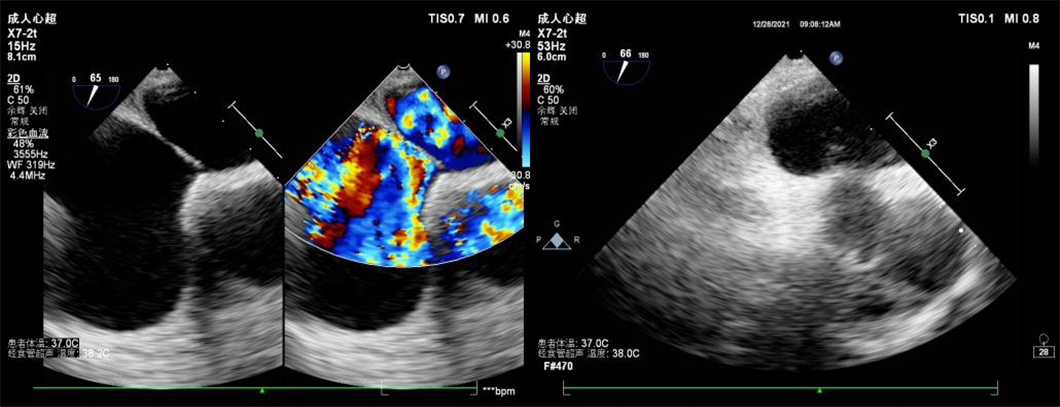

检查前,超声科医师充分了解两位患者基本情况,综合评估患者条件。患者1,女性,31岁,因头痛数年,加重4天就诊,门诊行经颅多普勒发泡实验阳性,为排除心脏疾患,行经食管超声心动图检查。患者2,女性,42岁,因头痛头晕数年,经胸超声心动图提示房间隔瘤形成,为进一步明确诊断,行经食管超声心动图检查。

患者2

据了解,部分患者行经胸超声心动图检查时,因自身条件、检查方式等客观原因,导致较小的心脏疾病容易漏诊。然而,经食管超声心动图检查作为经胸超声心动图的补充检查,可以更加直观、清晰地观察心脏内部结构,在先天性心脏病、瓣膜性心脏病、心脏肿瘤、血栓等疾病诊断中具有重要意义。尤其是在持续性头痛、不明原因脑卒中、动脉栓塞等患者中,可能会存在卵圆孔未闭这一心脏疾病。经食管超声心动图联合由右心声学造影检查可清楚显示卵圆孔的结构、大小、形态,分别在患者静息状态及Valsava动作下,通过观察房间隔卵圆孔处血流信号、造影剂微气泡的分流情况,准确诊断卵圆孔未闭,从而指导临床医生及时治疗,有效预防患者潜在脑血管意外事件的发生。